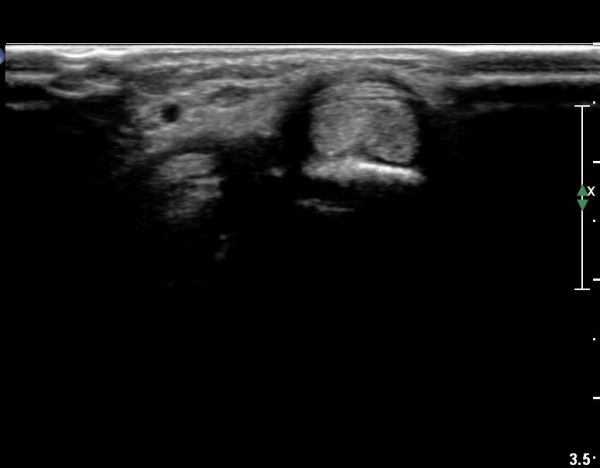

ŽÃËÀÚ¸¦¾à°£ ¿äÃøÀ¸·Î À̵¿ÇÏ¿© Àå¿äÃø¼ö±Ù½Å°Ç Á¾´Ü¸é°Ë»ç¿¡¼­ Àå¿äÃø¼ö±Ù½Å°ÇÀÇ

ºÎÁ¾ÀÌ °üÂûµÇ°í ½ÅÀü°Ç Ç¥Ãþ¿¡¼­ À幫Áö½ÅÀü°ÇÀÌ °üÂûµÈ´Ù(»çÁø 2).